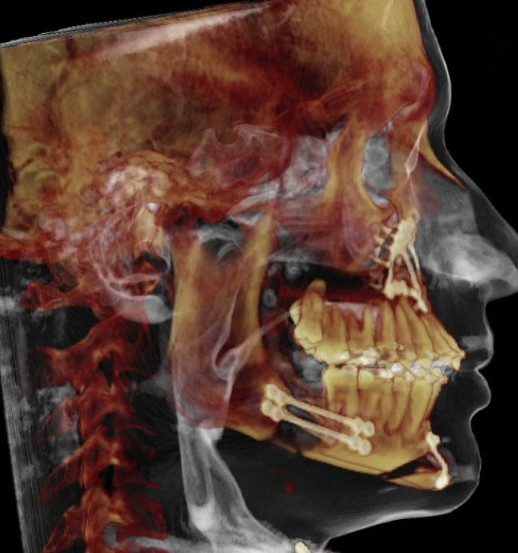

Lets be clear this is not hate, but doing bonegraft helps with not creating step offs and filling in gaps of leforts and bsso obv. Most of the time the gaps will be filled nonetheless to some degree but bone grafts is more of a guarntee. Also alfaro has many patients i have been in contact with where the bone didnt get healed fully because of huge movements and no bonegrafting and only anterior plates, ram does kinda the same except he dont do the same big movements.

And its more important if you do big bsso cuts, genios or maybe the most important one for big downgrafts of the maxilla.

Also some people might say that bonegraft dont show in ct/cbct, it def does

look in the pic below for example at the cuts shown with red circle:

Also some people might say that bonegraft dont show in ct/cbct, it def does

look in the pic below for example at the cuts shown with red circle: